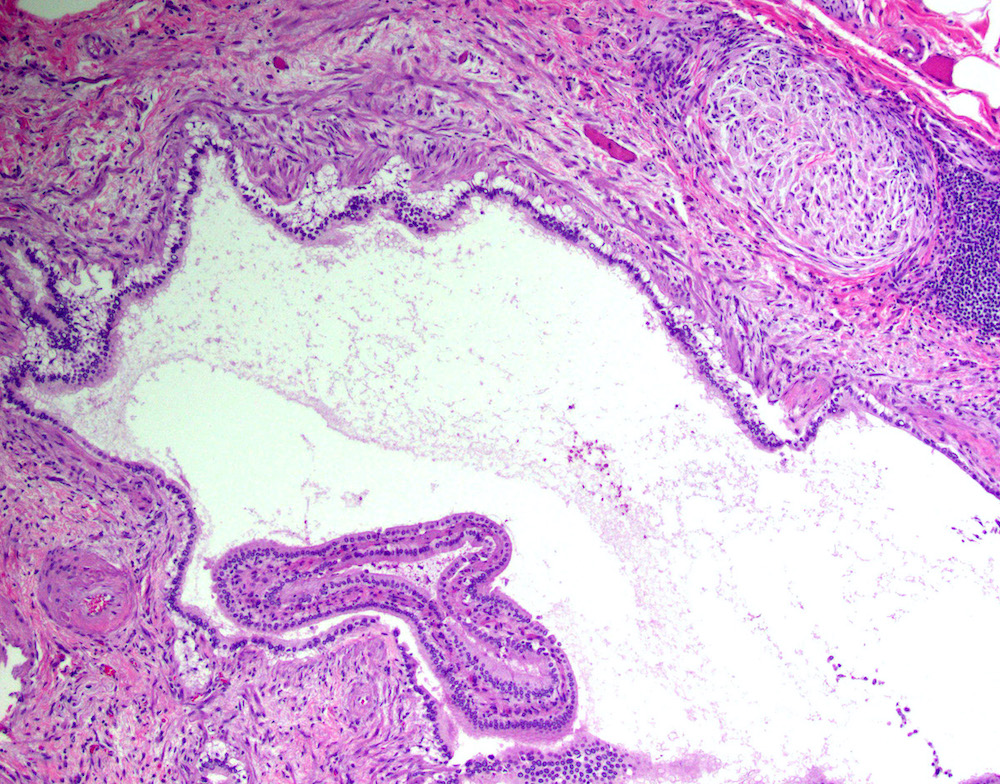

Microscopic (histologic) description

- Cystically dilated benign biliary glands accompanied by smooth muscle hypertrophy of gallbladder wall, thickened / fibrotic subserosa (StatPearls: Adenomyomatosis [Accessed 26 January 2021])

- Glands are distinct from the Rokitansky-Aschoff sinuses, which are epithelial diverticula, usually multifocal and occur throughout gallbladder secondary to injury, versus adenomyomatous nodule (distinct localized lesion of the gallbladder wall, 1 - 1.5 cm mural nodule in the fundus) (Am J Surg Pathol 2020;44:1649)

- May have reactive epithelial changes, papillary change and intestinal metaplasia (StatPearls: Adenomyomatosis [Accessed 26 January 2021])

Microscopic (histologic) images

Contributed by Monica T. Garcia-Buitrago, M.D.